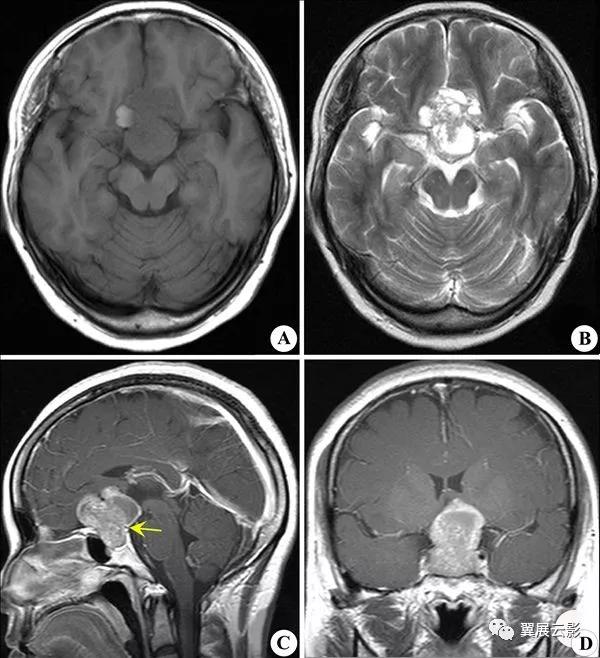

病例1:听神经瘤

MRI扫描表现为桥小脑角区圆形类圆形异常信号肿块,伴听神经增粗或内听道扩大,T1WI呈现等或低信号,T2WI呈现显著高信号,其内部含合并囊变时瘤体信号常不均匀,增强扫描肿瘤实体部分显著强化,囊变坏死区不强化,本病在重点描述病变的位置在桥小脑角区,肿块同侧听神经显著增粗及内听道扩大,平扫的信号特点及增强后表现,除描述直接征象外,尚需要描述周围结构受压,移位情况及有无脑水肿与幕上脑积水等。本病重点要与脑膜瘤,三叉神经瘤和胆脂瘤相鉴别。